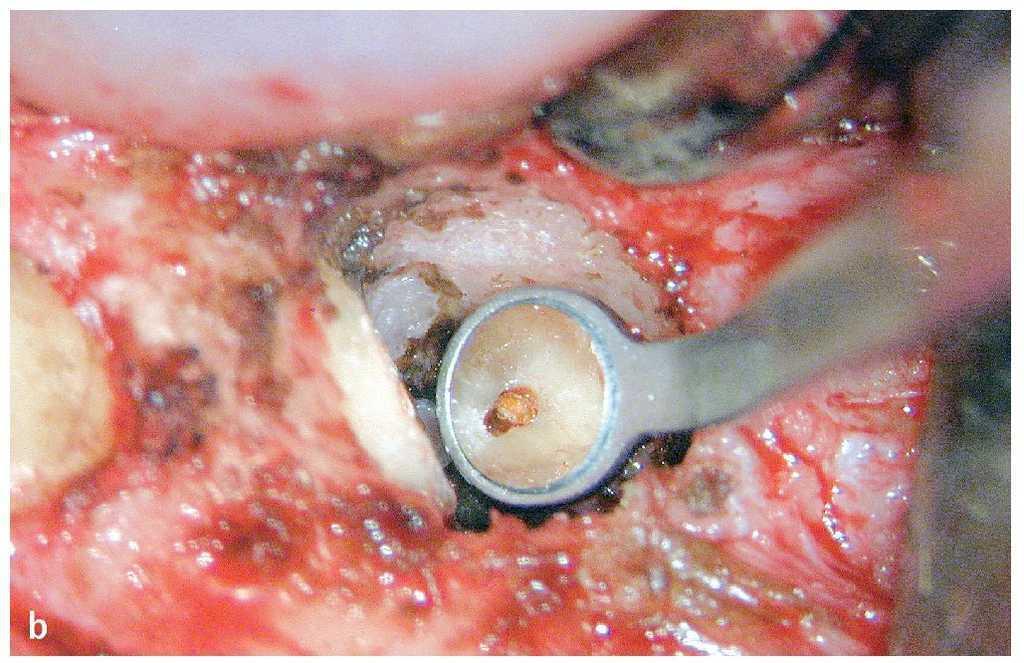

Figura 9a. En la radiografía se observa un anclaje insuficiente del perno, una obturación incompleta del conducto radicular, una reabsorción interna inmediatamente en apical del tercio medio radicular y un sellado retrógrado con amalgama después de una apicectomía.

Figura 9b. Después de retirar la corona y el perno intrarradicular y de la obturación se comprueba la ubicación de los restos de gutapercha existentes mediante una radiografía de control.

Figura 9c. Después de la remoción completa de la gutapercha queda a la vista el sellado retrógrado con amalgama y la laguna de reabsorción situada algunos milímetros por encima del sellado.

Figura 9d. Se eliminó el sellado retrógrado mediante ultrasonidos dejando al neoápice libre de restos de material.

Figura 9e. Se efectúa un control radiológico de la eliminación completa del sellado retrógrado.

Figura 9f. Una vez finalizada la preparación y después de una irrigación profusa con NaOCl asistida por ultrasonidos se procede al sellado apical con MTA (Dentsply DeTrey, Konstanz) con un grosor de capa de aproximadamente 4 mm. En la pared del conducto se visualiza claramente uno de los lados de la laguna de reabsorción.

Figura 9g. Control radiológico después del sellado apical con MTA.

Figura 9h. En un paso posterior se rellena la laguna de reabsorción desde apical a coronal mediante una técnica de inyección, reservando al mismo tiempo el espacio para el perno radicular previsto.

Figura 9i. Se realiza un nuevo control radiológico para comprobar la obturación homogénea completa de la laguna de reabsorción y, a continuación, se introduce un perno de fibra de cuarzo (VDW, Múnich).